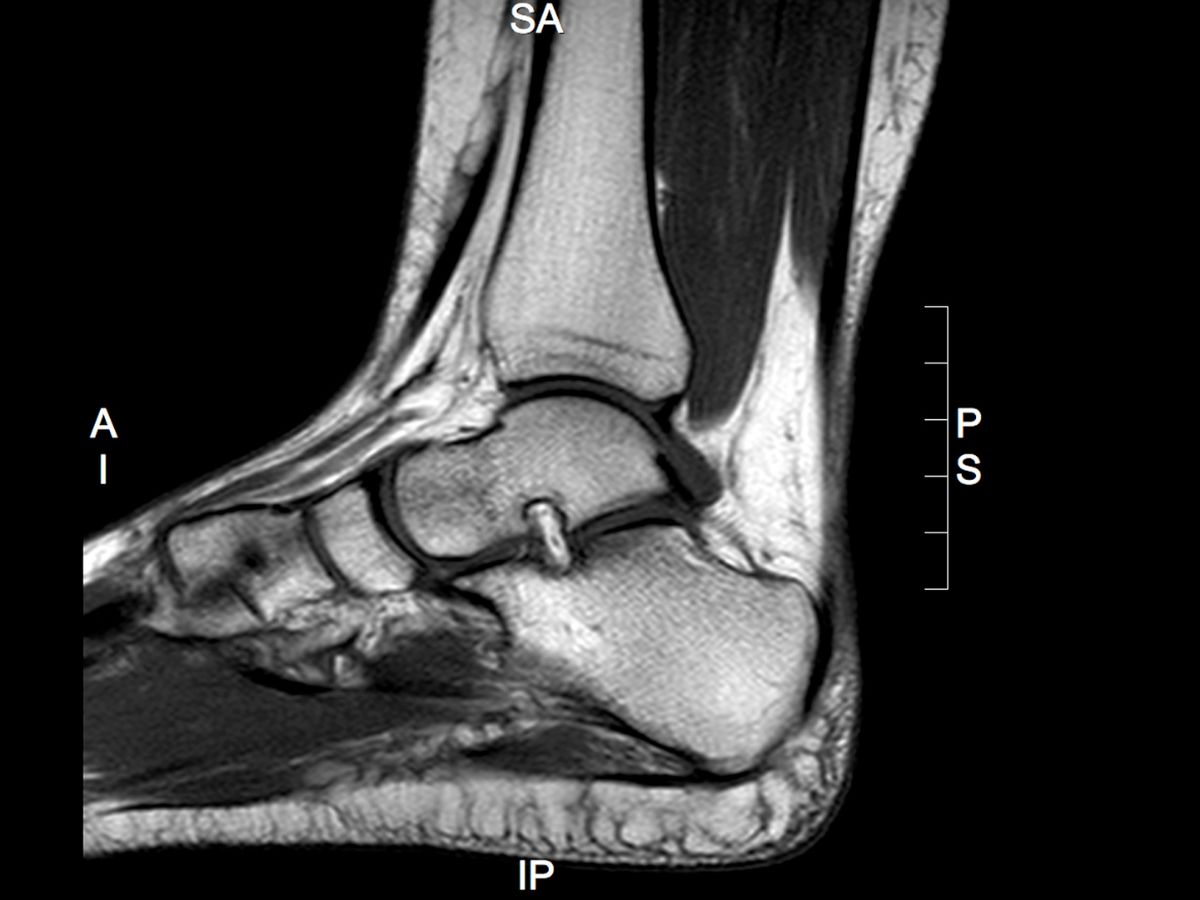

Clinician Resources